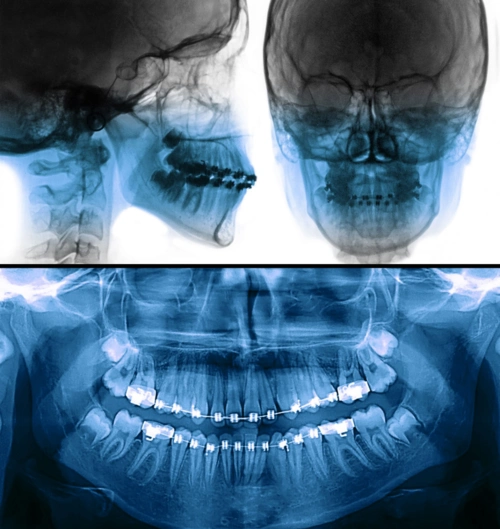

牙片一般分为全景片(也叫曲面断层)和根尖片,有些特殊的情况还需要拍

牙片详解,教你看懂牙片!_口腔_牙齿_全景

牙片怎么拍什么情况下医生会建议拍